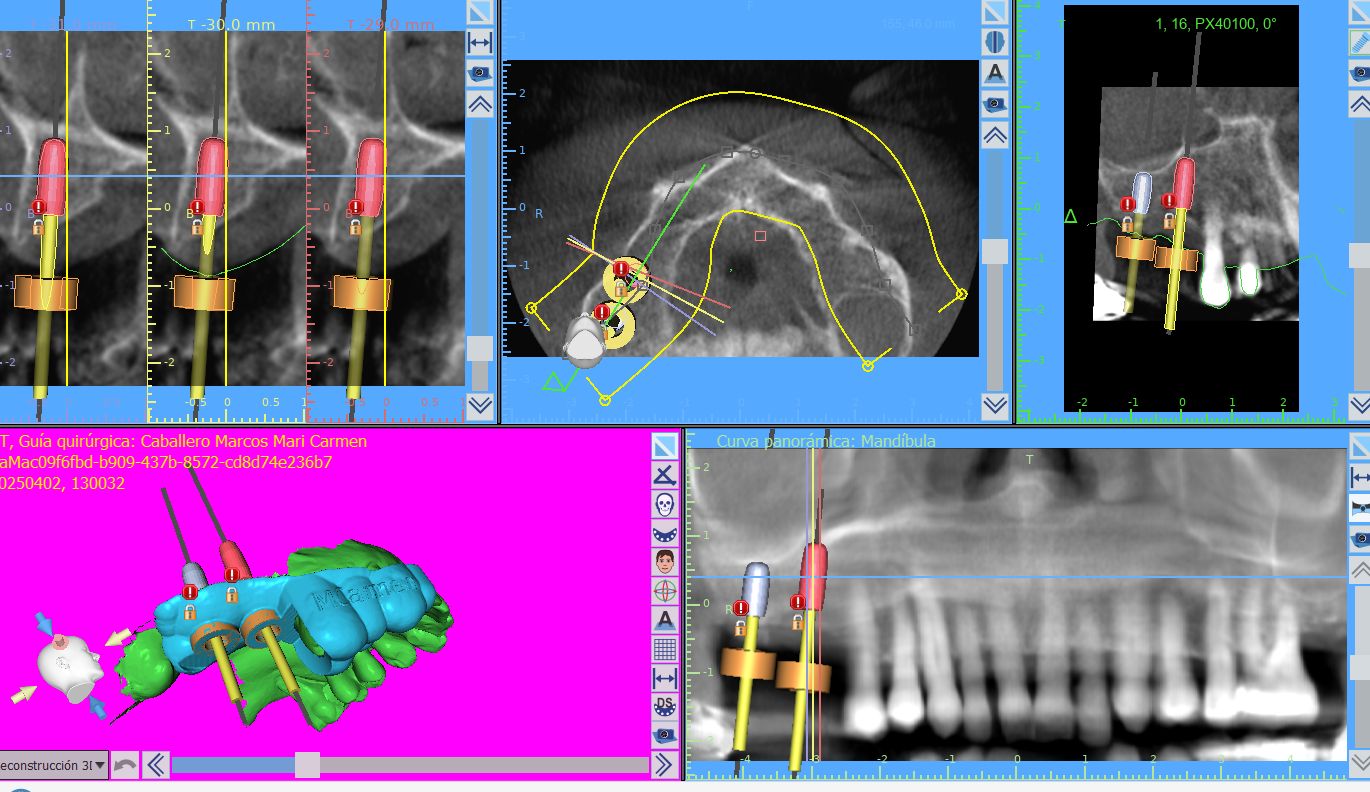

Cirugía guiada con férulas digitales:

Precisión quirúrgica, menos invasión, mejor postoperatorio. Recuperación más rápida. Lo planificamos todo digitalmente antes de tocar tu boca.